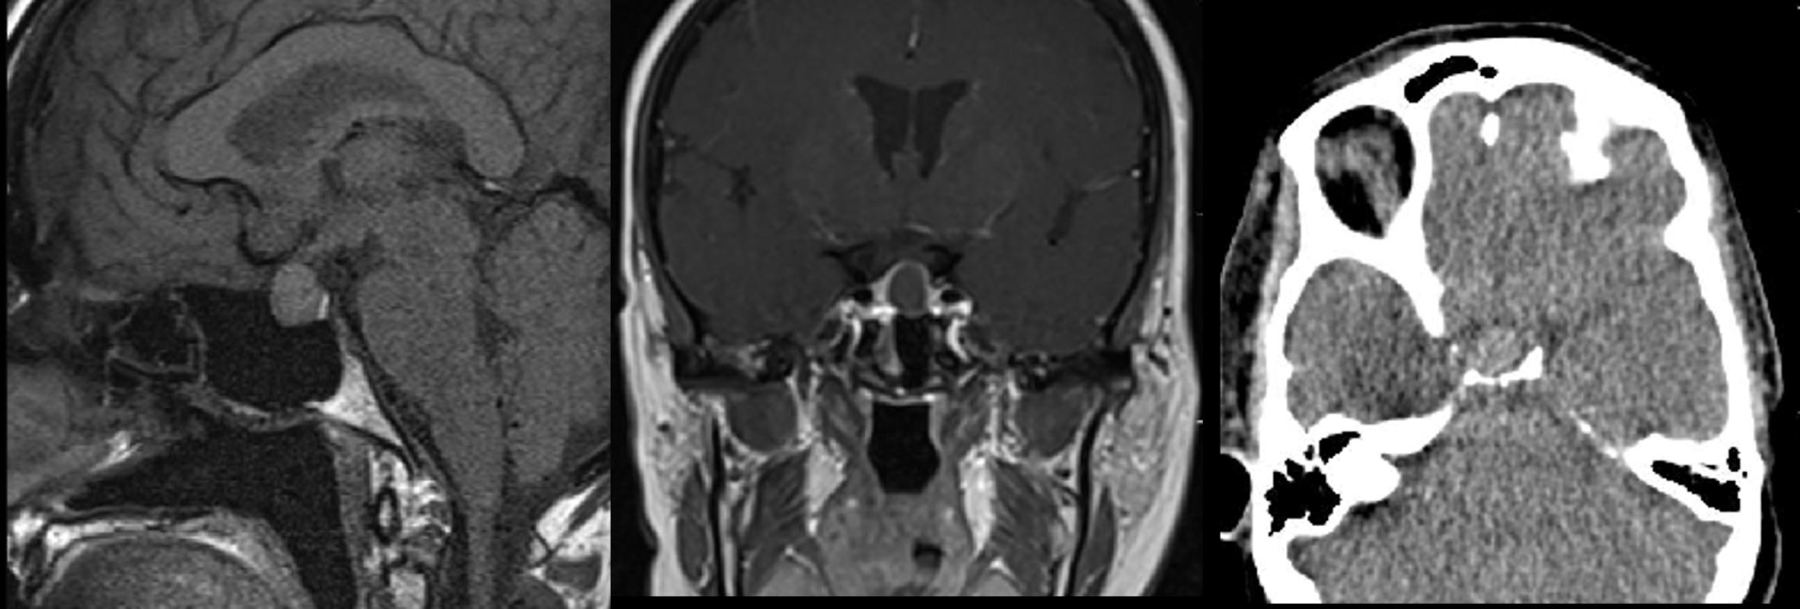

61 yaş, K

15-20 yıldır süren baş ağrıları, sağ göz görme alanında tam kayıp

Tuberkulum sella meningiomu